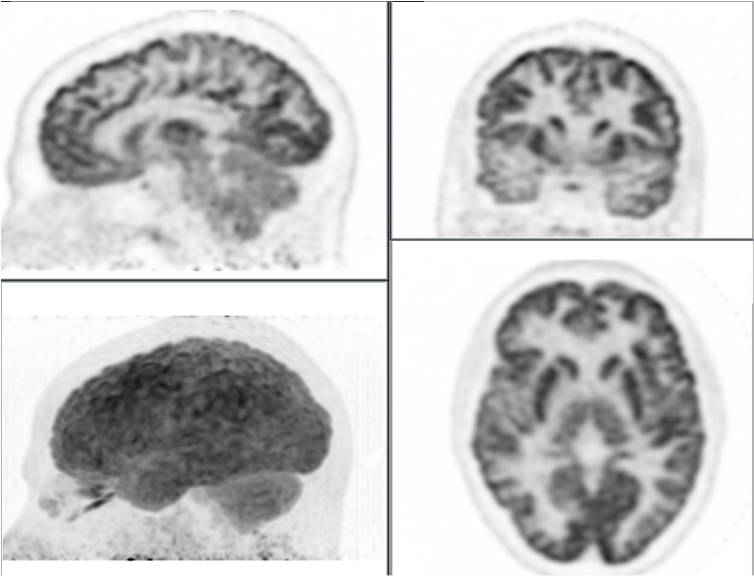

Included in the files are 2 pairs of brain scans. These represent the two comparisons between an older analogy technology and the breakthrough new digital technology from Philips.